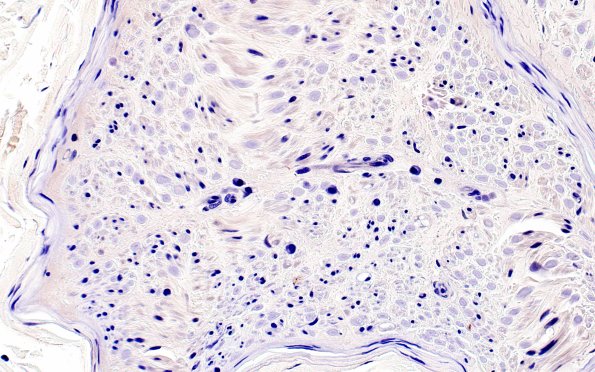

Washington University Experience | PERIPHERAL NEUROPATHY | 12 ANTI-MAG NEUROPATHY | 1B3 Anti-MAG Neuropathy (Case 1) Neg Control 40X 2

1B3,4 There are numerous plasma cells within the endoneurium. Do they correlate with the extent of myelinopathy by directly contributing to the intra-axonal titers of anti-MAG antibody? (negative immunostain)